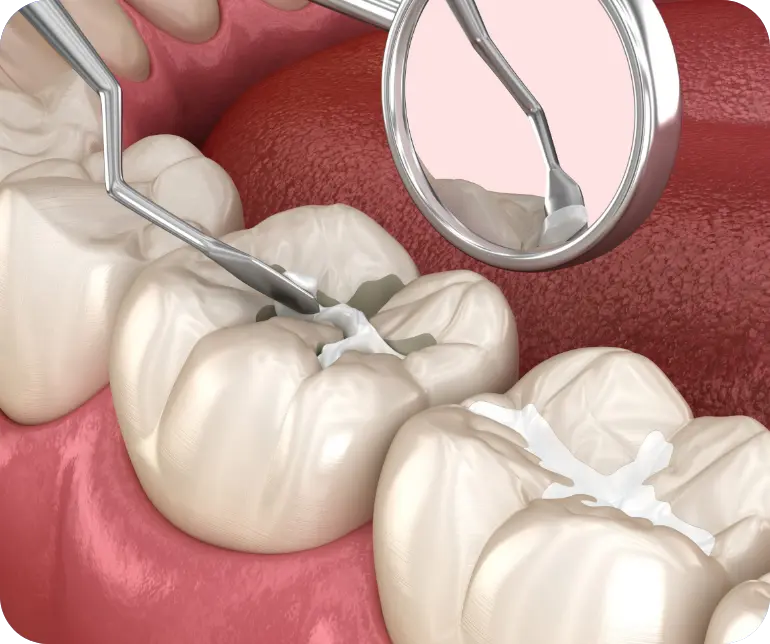

Vuoi prevenire la carie?

Scopri con noi la Sigillatura dei Solchi

Le sigillature dei solchi, pratica consolidata nell’ambito dell’odontoiatria preventiva, si configurano come un’azione proattiva fondamentale per preservare la salute dentale sia nei bambini che negli adulti.

Questo procedimento si distingue per la sua straordinaria efficacia nel preservare l’integrità dei denti, in particolare quelli più suscettibili, fornendo un robusto scudo contro l’aggressione batterica.